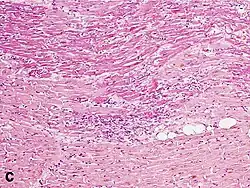

Micrograph of a myocardial infarction (ca. 400x H&E stain ) with prominent contraction band necrosis.

Under the microscope, myocardial infarction presents as a circumscribed area of ischemic, coagulative necrosis (cell death). On gross examination, the infarct is not identifiable within the first 12 hours.[22]

Although earlier changes can be discerned using electron microscopy, one of the earliest changes under a normal microscope are so-called wavy fibers.[23] Subsequently, the myocyte cytoplasm becomes more eosinophilic (pink) and the cells lose their transversal striations, with typical changes and eventually loss of the cell nucleus.[24] The interstitium at the margin of the infarcted area is initially infiltrated with neutrophils, then with lymphocytes and macrophages, who phagocytose ("eat") the myocyte debris. The necrotic area is surrounded and progressively invaded by granulation tissue, which will replace the infarct with a fibrous (collagenous) scar (which are typical steps in wound healing). The interstitial space (the space between cells outside of blood vessels) may be infiltrated with red blood cells.[22]

These features can be recognized in cases where the perfusion was not restored; reperfused infarcts can have other hallmarks, such as contraction band necrosis.[25]